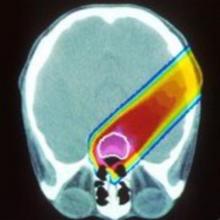

Chemoradiotherapy (CRT) refers to the combination of chemotherapy and radiation therapy. CRT is considered to be the standard-of-care treatment for many cancers. The treatments can have side effects including fatigue, nausea, vomiting, skin changes, and organ-specific damages. The side effects are … more